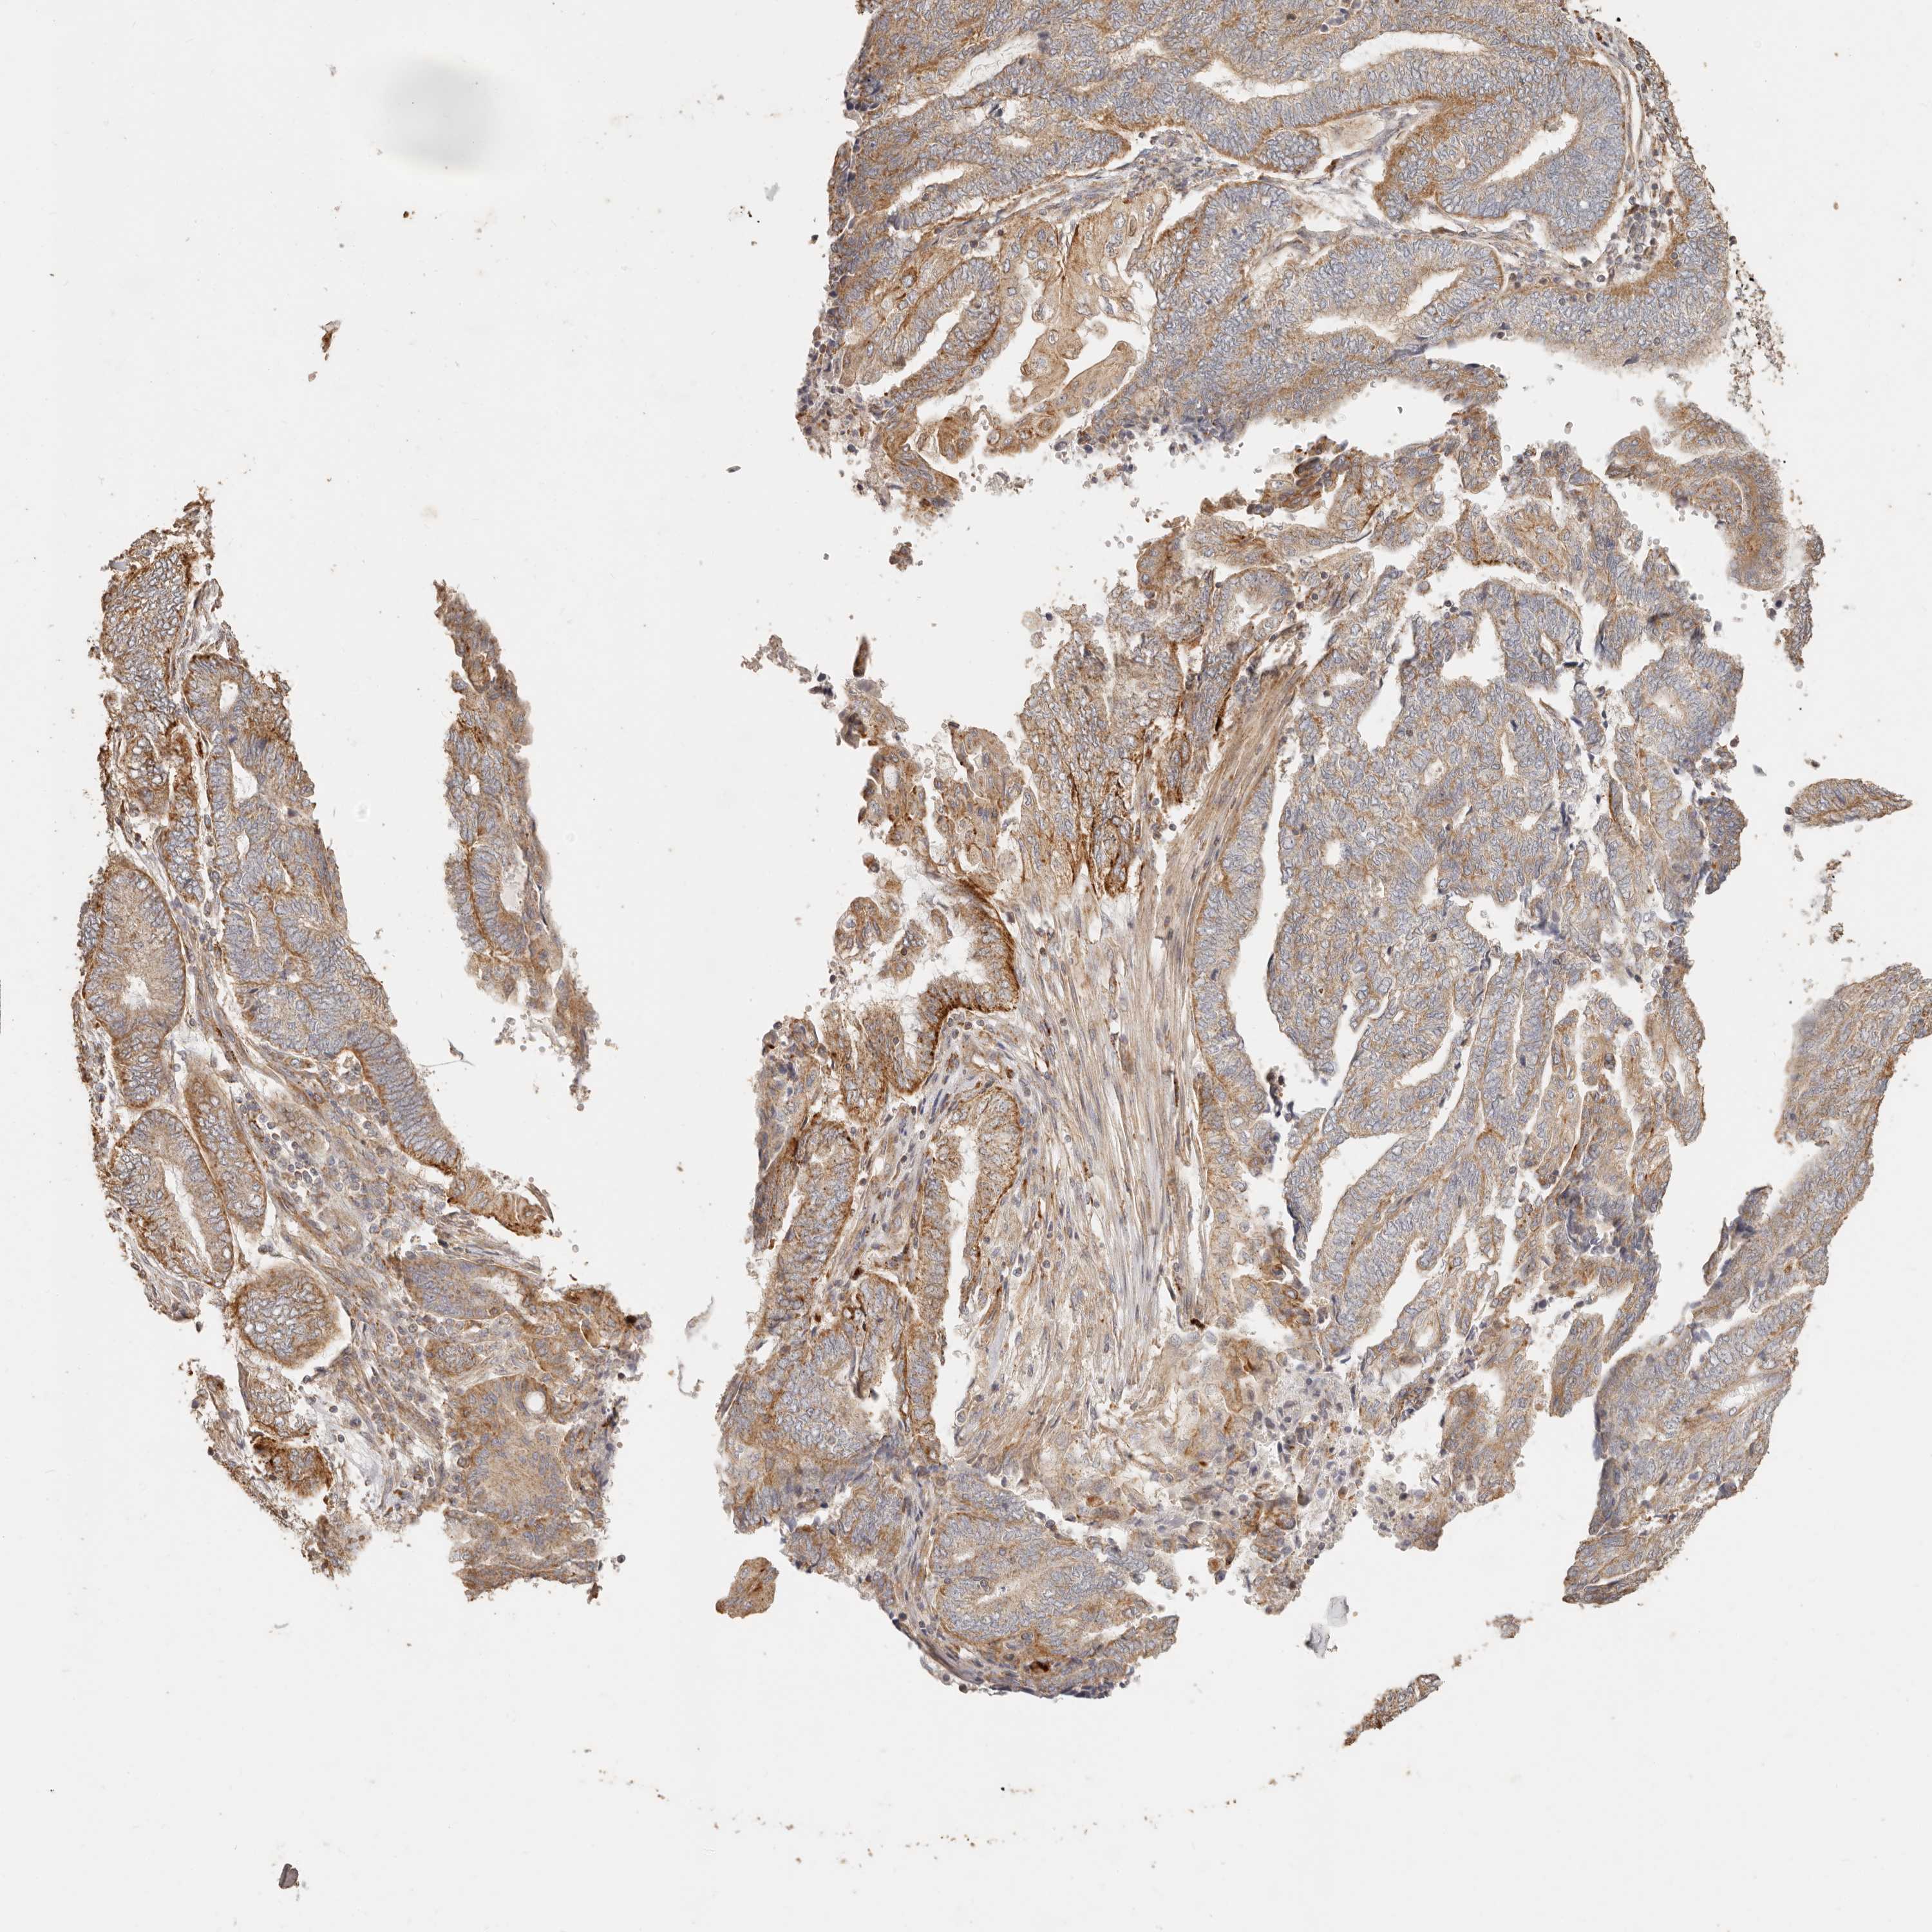

ENDOMETRIAL CANCER - Protein expressioni

A mouse-over function shows sample information and annotation data. Click on an image to view it in a full screen mode. Samples can be filtered based on level of antibody staining by selecting one or several of the following categories: high, medium, low and not detected. The assay and annotation is described here.

Note that samples used for immunohistochemistry by the Human Protein Atlas do not correspond to samples in the TCGA dataset.

Antibody stainingi

Antibody staining in the annotated cell types in the current human tissue is reported as not detected, low, medium, or high, based on conventional immunohistochemistry profiling in selected tissues. This score is based on the combination of the staining intensity and fraction of stained cells.

Each image is clickable and will lead to virtual microscopy that enables deeper exploration of all samples and also displays staining intensity scores, fraction scores and subcellular localization as well as patient and tissue information for each sample.

Antibody HPA004912

Antibody HPA013350

Antibody CAB012209

Staining

High

Medium

Low

Not detected

Intensity

Strong

Moderate

Weak

Negative

Quantity

>75%

75%-25%

<25%

None

Location

Nuclear

Cytoplasmic/membranous

Cytoplasmic/membranous,nuclear

Adenocarcinoma, NOS

Adenocarcinoma, metastatic, NOS